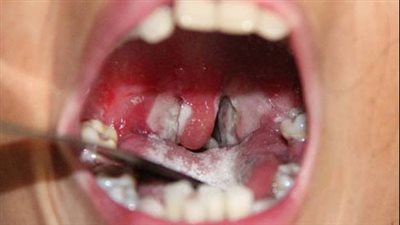

دراسة: معجون الأسنان يعطل بيئة الميكروبيوم الفموي ويضر بصحة اللثة

الإثنين 03/03/2025 12:25 م